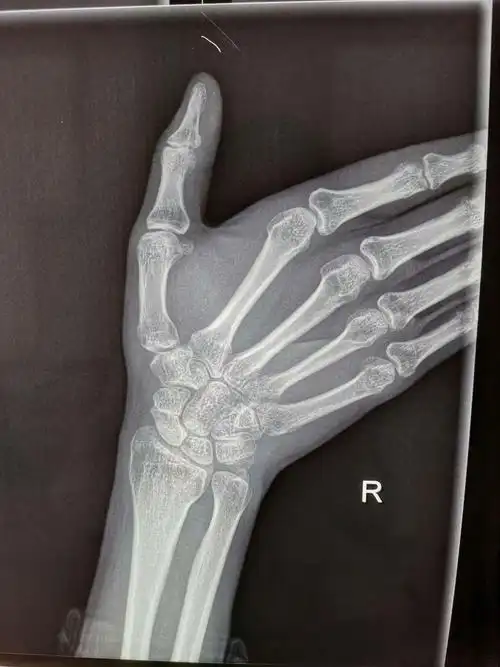

郑州市骨科医院会诊病例 腕舟骨骨折

腕舟骨骨折